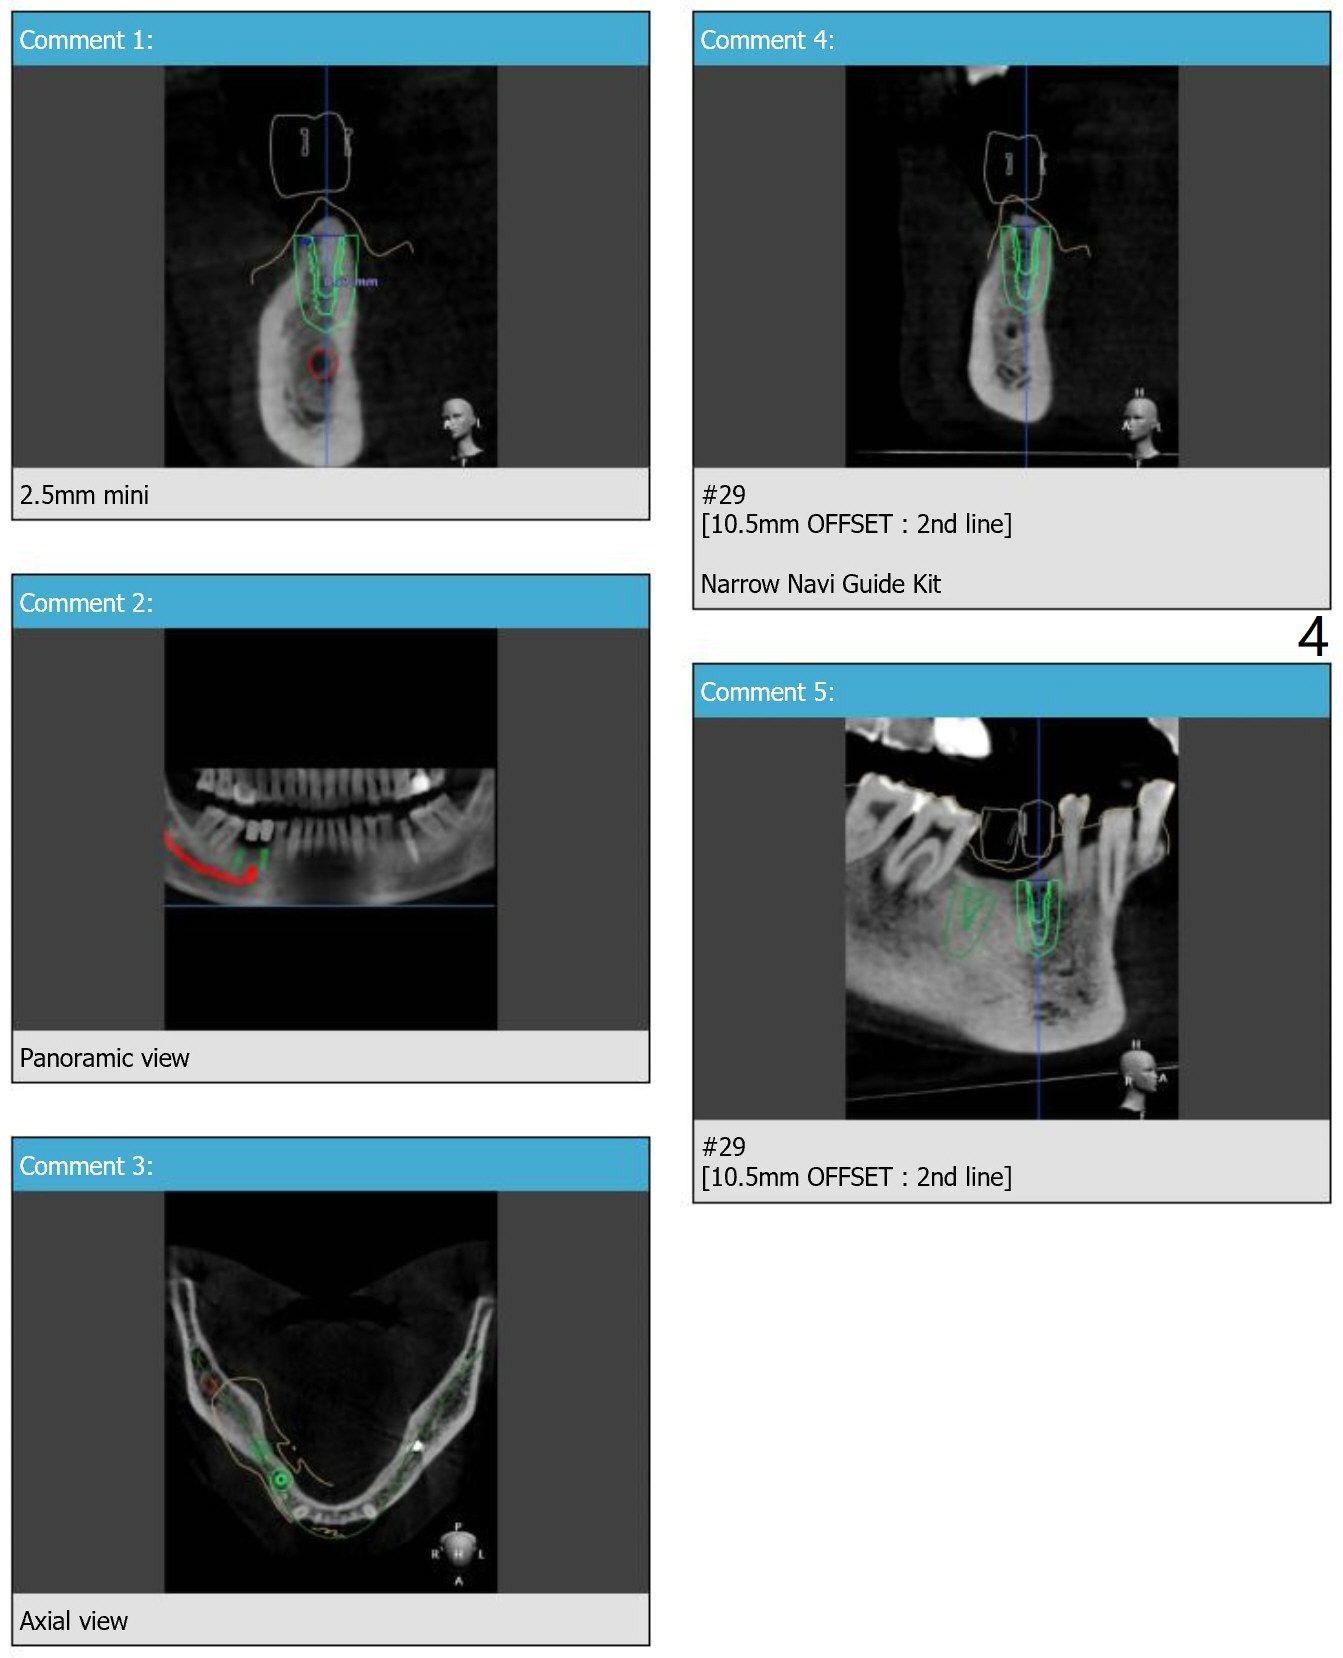

A 63-year-old man requests implant(s) at #29 and 30 to replace the lower RPD after implants at #15 and 19 (Fig.1). Because of the narrow mesiodistal space, two bicuspids will be fabricated. Due to the narrow buccolingual width, a 2.5 mm 1-piece implant will be placed at #30 (Fig.3, 5). The latter will be tilted to avoid the Mental Foramen.